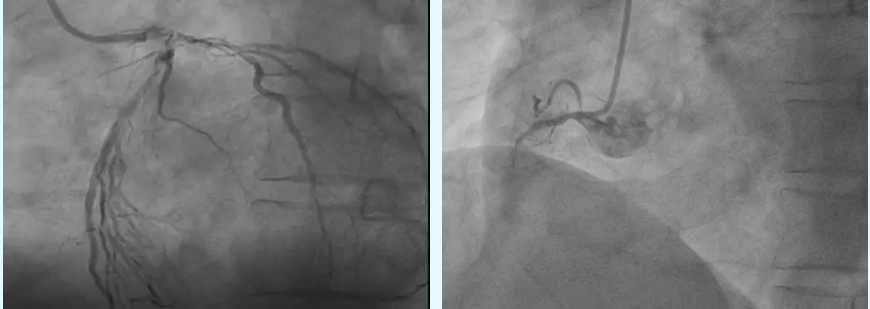

患者因反复心前区疼痛入院,一个月前曾发作急性心肌梗死,冠脉造影显示心脏三支主要血管重度狭窄,常规介入治疗已难以解决。经多学科会诊及充分术前准备,王忠明教授决定采用不停跳冠状动脉搭桥(OPCABG)方案。术中,团队取患者自身乳内动脉、大隐静脉作为桥血管,在心脏持续跳动的状态下,通过心脏固定器精准完成血管桥接,为心脏重建供血通道。在麻醉科、重症医学科等多学科医护团队密切配合下,手术顺利完成,患者术后一天便拔除气管插管转入普通病房,恢复良好,症状显著改善。相较于传统心脏停跳搭桥手术,不停跳冠状动脉搭桥(OPCABG)无需体外循环支持,避免了心脏停跳可能导致的心肺功能、肝肾功能及大脑功能潜在损害,不仅拓宽了冠脉搭桥手术的适应症,更具备三大核心优势:一是创伤更小,省去传统手术大切口及体外循环相关操作,有效减轻患者身体损伤;二是恢复更快,术后患者可更早开展康复训练,加速回归正常生活节奏;三是并发症更少,大幅降低术后心肺功能不全、肝肾功能损害等不良事件的发生率,为患者康复筑牢安全防线。作为云南省心脏外科领域标杆人物,王忠明教授深耕行业多年,曾任职于多家三甲医院心外科主任,主刀各类心脏手术超万例。他先后赴美国、德国、新加坡等国顶尖医学中心交流学习,将国际前沿技术与中国患者实际需求深度结合,形成了兼具精准性与实用性的诊疗体系,以实打实的技术实力赢得了患者 “性命相托” 的信赖。如今,无需跨省奔波,在曲靖就能享受到国内顶级心外科服务。无论是先天性心脏病患儿、冠心病及心肌病变中老年人,还是需心脏瓣膜修复/ 置换的重症患者,或是受外周血管疾病、缩窄性心包炎等罕见病困扰的人群,均可在云南省曲靖中心医院获得王忠明教授团队量身定制的诊疗方案,大幅节省时间与经济成本。心脏健康无小事,及时诊疗是关键。王忠明教授以精湛医术为曲靖及周边地区群众筑牢“心”防线,让更多患者在家门口就能抓住“心”生希望,守护生命健康。医院将持续生动践行“着力打造一所‘无差别诊疗’的品质医院,一所自己父母不找熟人也能舒心看病的一流医院”的院景。不断提升医疗技术水平与服务质量,为广大心血管疾病患者提供更优质、高效的医疗服务,助力推进区域心血管疾病防治事业高质量发展。